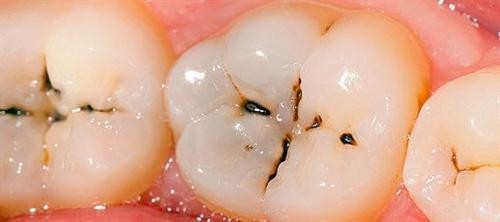

2、龋齿

当牙齿遭受致龋菌侵蚀的时候,一般初期会出现脱矿,牙齿局部发白,尔后随着时间推移渐渐变成黑点、黑线。

当发现牙齿已经存在明显的黑点黑线,可以及时到正规的口腔医院检查,如果确认龋坏的话,根据医生建议及时进行补牙修复。